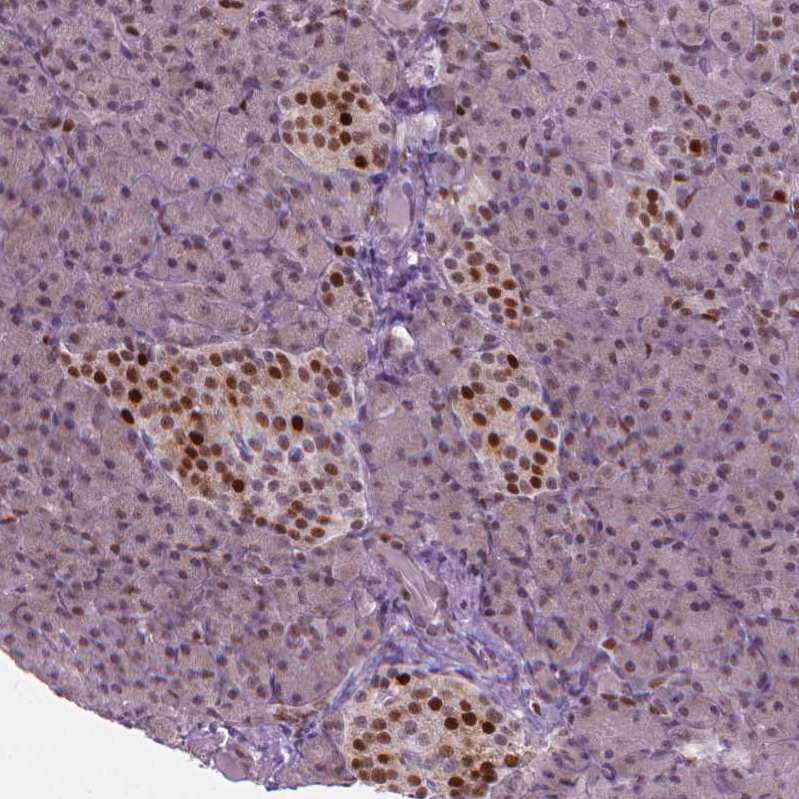

Immunohistochemistry analysis in human placenta and lymph node tissues using HPA002924 antibody. Corresponding CDKN1C RNA-seq data are presented for the same tissues.